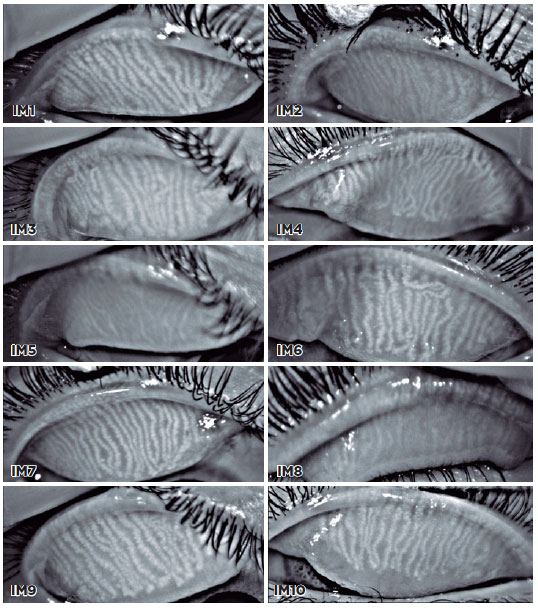

A total of 10 meibography images were selected, and 11 viewers were asked to grade the images using the proposed scale (Figure 2). The viewers were divided into three groups: (A) ophthalmologists with experience with meibography, (B) ophthalmologists with no experience with meibography, and (C) radiologists. Radiologists were selected as they use different and new grading scales every day. The kappa statistic was determined to test interrater reliability for all participants and between the groups using software StataCorp (Stata Statistical Software: Release 14. College Station, TX). A kappa score of 0.41-0.60 indicated low reliability; 0.61-0.80, moderate; and >0.81, high.

The proposed score ranged from 1 to 3 according to the MG morphology regarding gland internal reflectivity and gland margin delineation (Figure 1). Grade 1 represented a gland without alterations and was determined by high internal reflectivity and a well-defined contour exhibiting good contrast with the adjacent stroma. In grade 2, a decrease in internal reflectivity was observed (light gray), but the gland margins remained easily identifiable (if desired, the gland width could still be easily measured). Grade 3 was determined by low internal reflectivity and unclear gland margins. In this grade, the glands were very pale, almost the same grayscale level as the adjacent stroma, making it very difficult to measure their width. The rationale for creating a three-category scale was observational. Most of the patients exhibited a grade 1 score before starting isotretinoin treatment, and grades 2 and 3 reflected the range of postmedication atrophy that was observed.